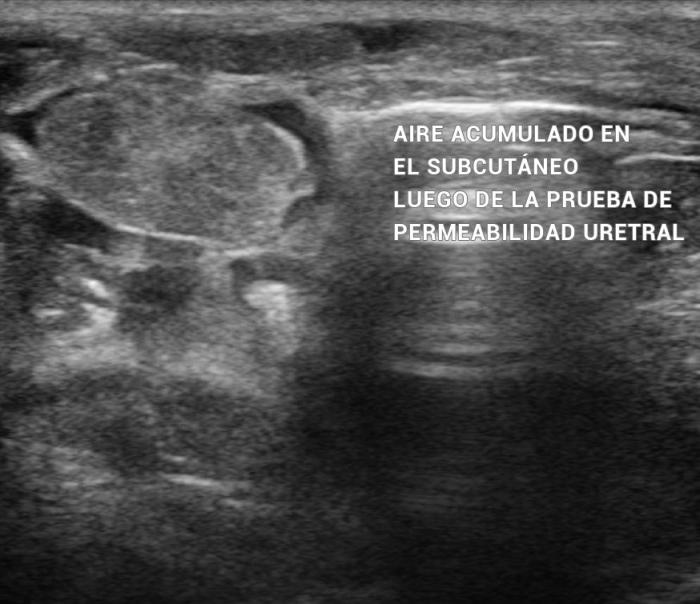

Mediante el estudio ultrasonográfico se detectó la presencia de líquido acumulado en la cavidad pélvica, en la zona peri-uretral, con esteatitis asociada (Figura 5). Debido a estos hallazgos se sospechó una ruptura traumática de la uretra, por lo cual se sometió a la paciente a una prueba de contraste uretral positivo, la cual evidenció la perforación uretral (Figura 6).

Luego de un corto tiempo, el aire introducido se acumula en el subcutáneo (Figura 7) (Vídeo 2).